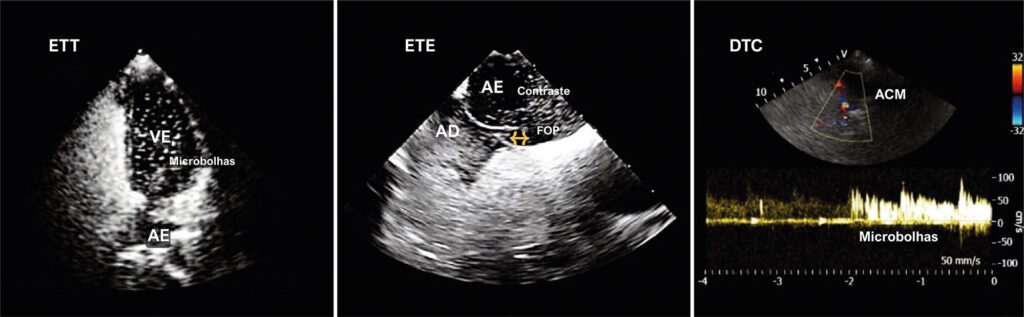

Este artigo de revisão explora o uso combinado do Doppler Transcraniano (DTC) com ecocardiograma transtorácico (ETT) e transesofágico (ETE) para investigar o Forame Oval Patente (FOP), uma condição encontrada em cerca de 25-27% da população adulta. O FOP é um remanescente da circulação fetal e a causa mais comum de shunt interatrial. Está associado a complicações clínicas como síndrome de platipneia-ortodeóxia, apneia do sono obstrutiva, enxaqueca e acidente vascular cerebral (AVC).

A avaliação do FOP é geralmente realizada por meio de ETT e ETE, mas o DTC, um método de alta sensibilidade e menos utilizado, também é importante. O DTC detecta shunts de forma indireta em pacientes acordados e utiliza o escore de graduação de sinais microembólicos (MES) para classificar a gravidade do shunt. A técnica envolve a injeção de uma solução de contraste na veia antecubital durante a manobra de Valsalva, onde o aparecimento de microbolhas nos primeiros ciclos cardíacos indica um shunt intracardíaco.

Relato de caso que ilustra a eficácia do DTC no rastreamento inicial de um paciente com suspeita de FOP, utilizando ETT, DTC e ETE. A conclusão destaca o papel crucial do DTC como uma ferramenta diagnóstica, especialmente relevante no manejo terapêutico de pacientes com AVC criptogênico. O estudo faz referência a várias publicações científicas, proporcionando uma base teórica para o uso combinado de DTC, ETT e ETE na investigação de FOP.